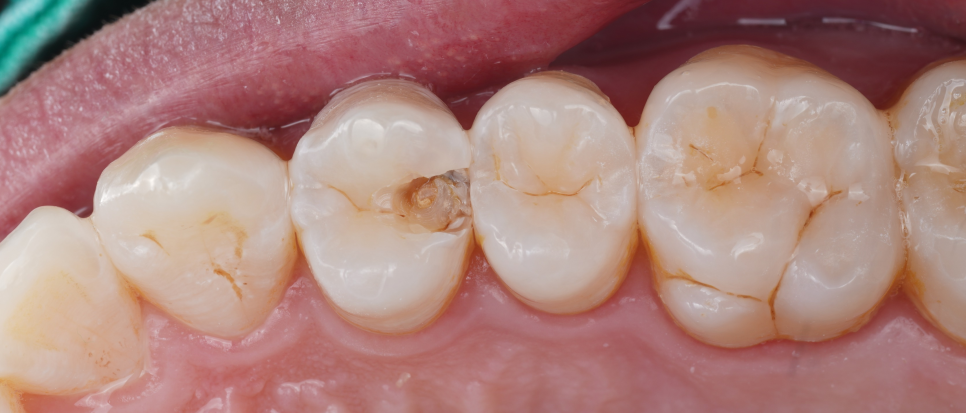

생각보다 파절 부위가 커서 걱정이 됐는데요.

기존 재료를 제거한 뒤 확인해 보니 다행히 신경까지는 진행되지 않아서 크라운으로 덮지 않고 레진으로 충분히 복원 가능한 상태라 판단이 들었어요.

레진의 큰 장점은 ‘최소삭제’예요.

필요한 부분만 아주 조심스럽게 제거하고 치아 본래의 구조를 최대한 보존할 수 있죠.

촬영일 : 251020

반면 인레이나 크라운은 충치가 있든 없든 치아 전체를 덮어야 하니 자연치가 많이 깎일 수밖에 없는데요.

그래서 이번에도 굳이 크라운으로 가지 않고 레진 빌드업으로 다시 살려보기로 결정했죠.

충치 부위를 깨끗하게 제거한 뒤 Se-bond를 사용해 접착층을 형성하고 여러 층으로 쌓아 올렸어요.

각 층마다 빛을 이용해 단단하게 굳힌 뒤 자연치와 같은 질감과 색을 만들어냈죠^^